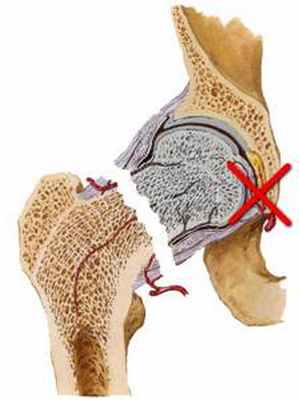

Переломы вертлужной впадины возникают в результате высокоэнергетической травмы (например, при падении с высоты или автомобильной аварии). Переломы вертлужной впадины, если они смещенные или если после закрытой репозиции сохраняется нестабильность, лечат хирургически. Переломы вертлужной впадины с повреждением задней стенки лечат нехирургическим путем. При этих травмах рекомендуется консультация ортопеда.

Выбор доступа зависит от типа перелома и общего состояния пациента. Пространственное представление расположения костных фрагментов является неотъемлемой частью предоперационного планирования. Для предупреждения некроза кости необходимо бережно относиться к мягким тканям. Следует обеспечить защиту жизненноважных нервов и сосудов. Костные фрагменты должны быть с максимальной точностью сопоставлены и стабильно фиксированы, как правило, шурупами и пластинами, которые не должны соприкасаться с суставной поверхностью. Возможность проведения операций под контролем усилителя рентгеновского изображения (ЭОП) позволяет правильно расположить ортопедические металлоконструкции в области вертлужной впадины. По мере накопления опыта оперативного лечения происходит снижение частоты осложнений и неудовлетворительных результатов.